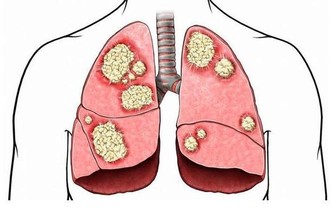

中醫認為,口乾、口苦是肝膽火旺的典型症狀。當人體的肝臟功能出現問題時,體內的代謝物、毒素、垃圾就不能及時排出並且堆積,從而引起口苦。

另外,很多時候,膽囊疾病病人都有口苦的現象。尤其是老年人,由於胃動力差或者膽汁反流所引起口苦。